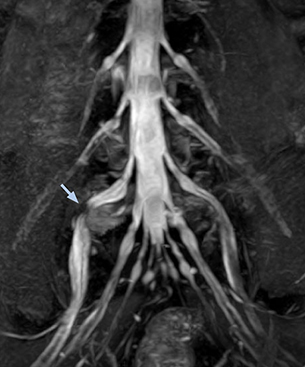

“In such case, we would then browse through axial T2-weighted MR images slice by slice and mentally reconstruct the actual situation based on both radiculography and MRI. Fortunately, NerveVIEW can now very well show nerve courses and presence of nerve compression or edema in one single image series.” “We have often seen NerveVIEW directly depict details of the nerve compression that were not observed by radiculography. Therefore, we think that with NerveVIEW we can reduce the number of invasive examinations, especially for some patients with lumbar plexus symptoms.”

The key concept in MR neurography, Dr. Yabuki stresses, is the ability to directly visualize spinal nerves, versus inferring the presence of pathology indirectly. “Before NerveVIEW, we estimated compression of the nerve by looking for the presence or absence of fat signal on other MR images,” he says.

“For example, in sagittal images, when the presence of fat is observed in the intervertebral foramen, it suggests that there is a margin around the nerve. Similarly, the absence of fat indicates that the nerve is being compressed. So, we used to deduce nerve compression indirectly. With NerveVIEW, however, we can observe the condition of the nerves directly, regardless of the presence or absence of fat. We always prefer such direct observation of anatomy over having to make an inference about it.”

“Although symptoms of typical disc herniation and atypical hernia are very similar, the actual site of herniation is different. It is therefore important to characterize the nerve’s condition both inside and outside of the intervertebral foramina. “Conversely, if we see no abnormality in NerveVIEW, we can assume at least that there is no severe condition that requires surgery. Like this, it can help us avoid unnecessary surgery. NerveVIEW can have a tremendous impact in this way.”